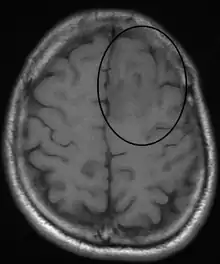

Oligodentroglioma arise mainly in the frontal lobe and in 50-80% of cases, the first symptom is the onset of seizure activity. Headaches combined with increased intracranial pressure are also a common symptom of oligodendroglioma. Depending on the location of the tumor many different neurological deficits can be induced, including, but not limited to, visual loss, motor weakness and cognitive decline. A computed tomography (CT) or magnetic resonance imaging (MRI) scan is necessary to characterize tumor size, location, and hetero- or homogeneity. Final diagnosis relies on biopsy and histopathologic examination of the tumor mass.